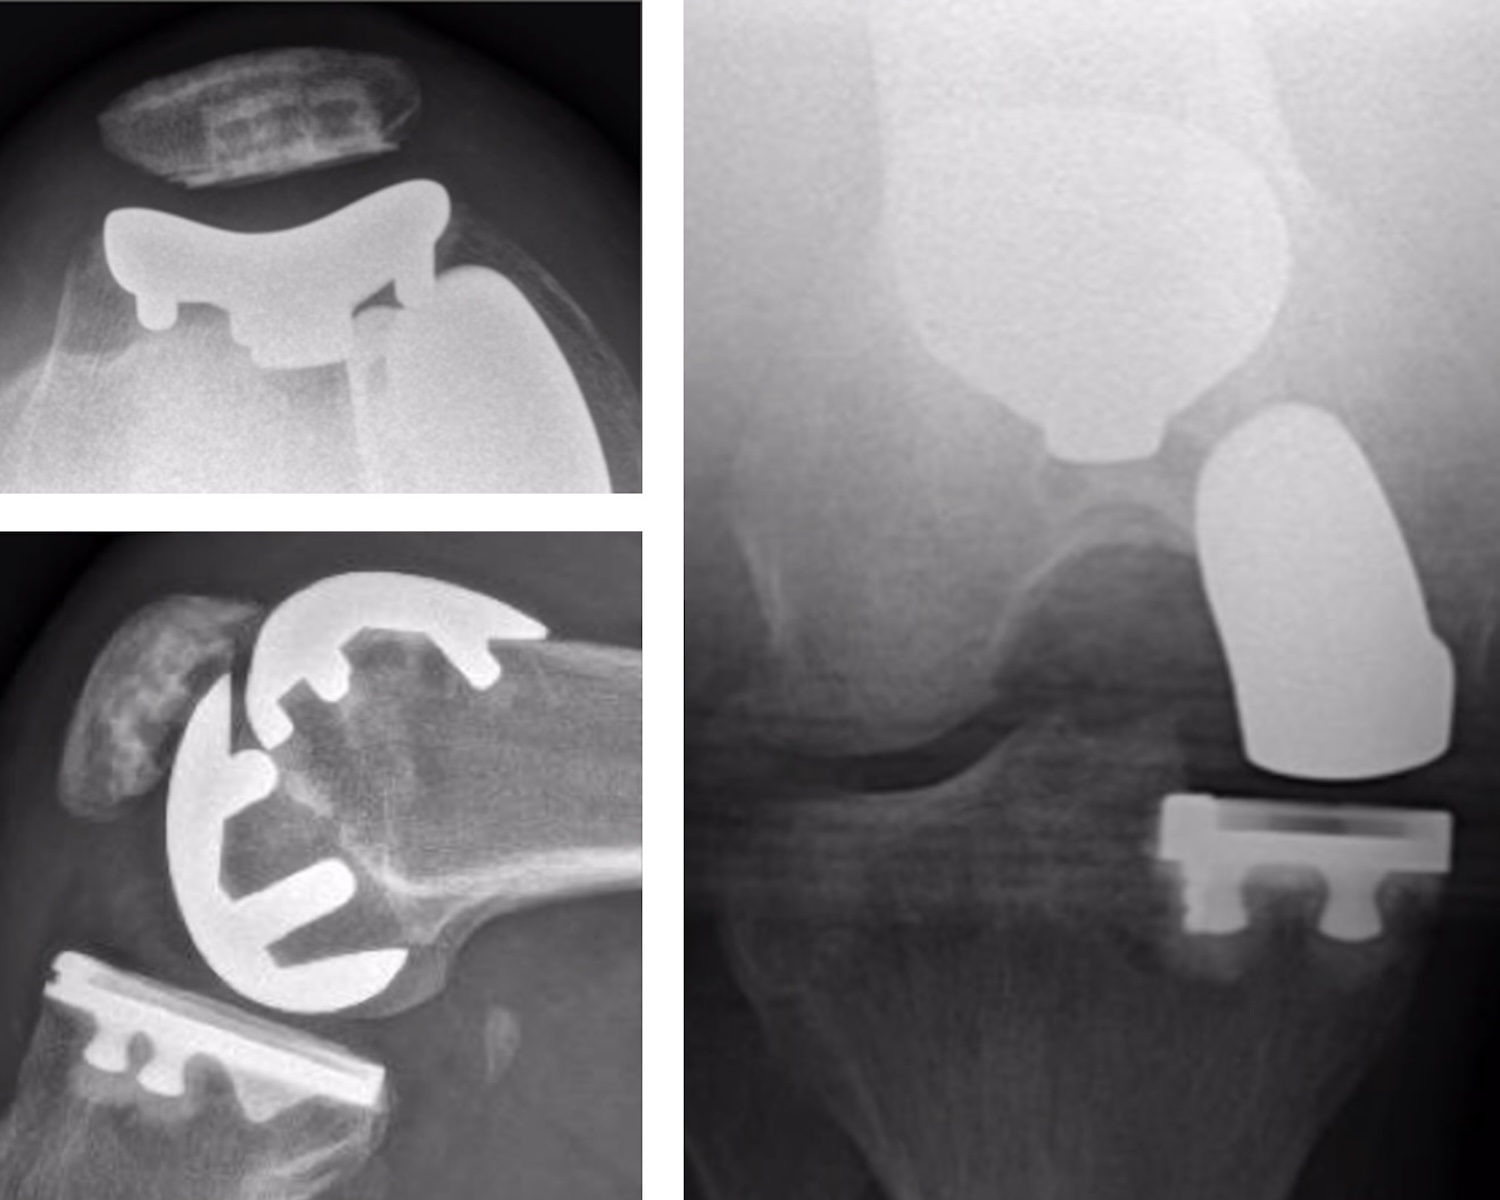

PD Dr. von Knoch hat sich auf die patientenspezifische und minimalinvasive chirurgische Behandlung von Knie- und Hüftproblemen, insbesondere der Arthrose, spezialisiert. Beim Kniegelenkersatz (Knieprothese) verwendet PD Dr. von Knoch — wenn immer möglich — Knieteilprothesen (Teilgelenkersatz) in einem der drei oder kombiniert in mehreren Kniekompartimenten, bei Bedarf kombiniert mit arthroskopischen Operationstechniken. Diese Strategie hat zum Ziel wichtige, nicht von der Arthrose betroffene Gelenkstrukturen inklusive Kreuzbänder zu erhalten und somit ein möglichst natürliches Kniegefühl und eine hohe Kniefunktion wiederherzustellen.

Bei komplexerem Kniearthrosemuster werden Knietotalprothesen der neuesten Generation mit patienten-spezifischer Weichteilbalancierung und personalisierter Prothesenausrichtung und ‑dimensionierung verwendet.

PD Dr. von Knoch hat sich auf die patientenspezifische und minimalinvasive chirurgische Behandlung von Knie-und Hüftproblemen, insbesondere der Arthrose, spezialisiert. Beim Kniegelenkersatz (Knieprothese) verwendet PD Dr. von Knoch — wenn immer möglich — Knieteilprothesen (Teilgelenkersatz) in einem der drei oder kombiniert in mehreren Kniekompartimenten, bei Bedarf kombiniert mit arthroskopischen Operationstechniken.

Diese Strategie hat zum Ziel wichtige, nicht von der Arthrose betroffene Gelenkstrukturen inklusive Kreuzbänder zu erhalten und somit ein möglichst natürliches Kniegefühl und eine hohe Kniefunktion wiederherzustellen. Bei komplexerem Arthrosemuster werden Knietotalprothesen der neuesten Generation mit patienten-spezifischer Weichteilbalancierung und personalisierter Prothesenausrichtung und ‑dimensionierung verwendet. Hüftprothesen implantiert PD Dr. von Knoch minimalinvasiv mit direkt anterioren Hüftzugang (ohne Extensionstisch).